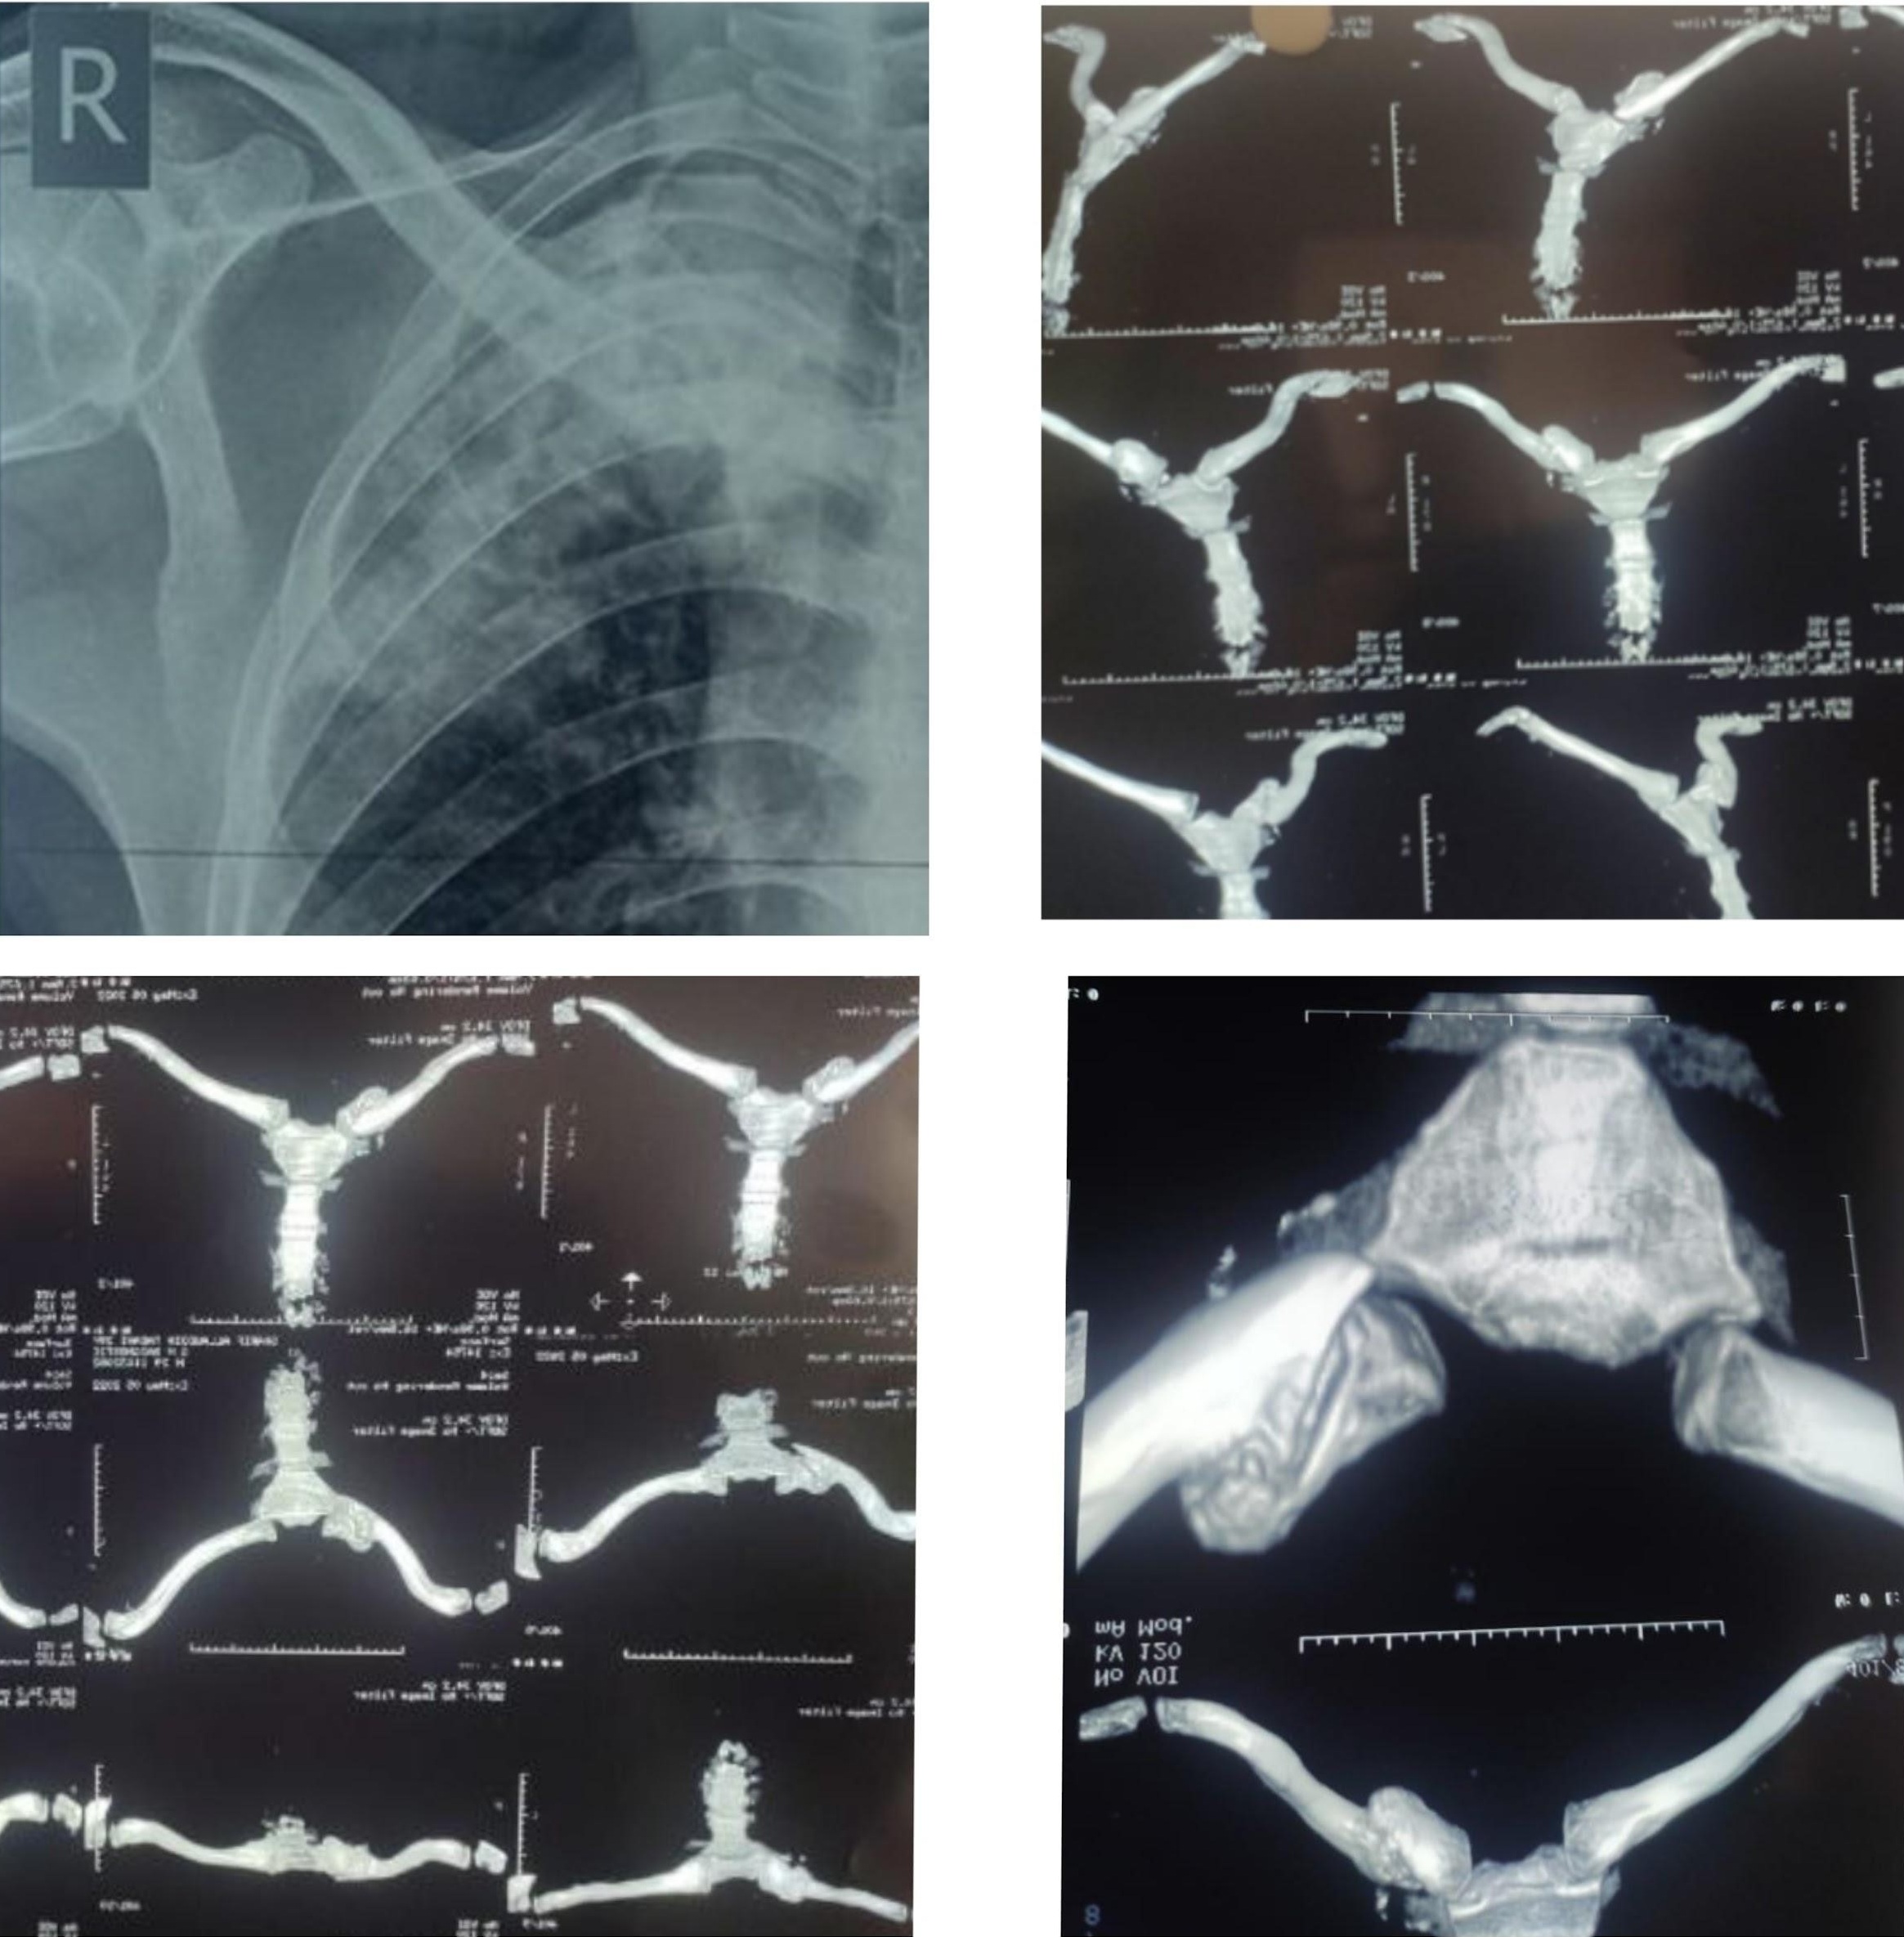

A 42-year-old male was referred from a regional center to our center for symptomatic abnormal prominence of the medial clavicle with non-union post-traumatic stress due to a fall under the influence of alcohol. The patient was a chronic alcoholic laborer from a remote village area. The patient sustained trauma in a drunken state on the right side of their clavicle. Initially, the patient didn’t consult for the trauma. The patient has taken local treatment in the form of medication and sling support for pain and swelling for 3 weeks. The patient is a laborer from a remote village area, and after 3 weeks, he resumed his work but was in some pain. The pain continued later on, and he noticed swelling over the medial end of the clavicle after a few months. The patient continued ice fomentation and pain medications for nearly 20–24 months. After almost 2 years, they came to our center for pain and sensation of instability at the fracture site with abnormal prominence fragments over the skin (Fig. 1). We have assessed him clinically and done the basic X-ray (Fig. 2a) and computed tomography (CT) scan (Fig. 2b, c, d) with 3D reconstruction. Range of movement at the shoulder joint abduction around 50° with pain further 20° is possible, rotation 30 external rotation and 40° of internal rotation with mobility in the vertical plane with mild tenderness (not significant) with neurological strength of abductor and rotator grade 4 might be due to pain and instability. Radiologically (X-ray and CT scan) found to be a non-union of the medial end of the clavicle with a tiny medial fragment with complete overlapping and abnormal prominence at the fracture site (poking skin). The patient is a laborer and wanted stable fixation with functional movement at the shoulder joint.

Figure 2: (a) Pre-operative X-ray showing non-union of the medial end clavicle fracture with overlapping fragments. (b) computed tomography (CT) scan axial view confirming non-union with a small medial fragment. (c) CT sagittal reconstruction showing complete overlap at the fracture site. (d) CT 3D reconstruction illustrating the extent of non-union and fragment anatomy.